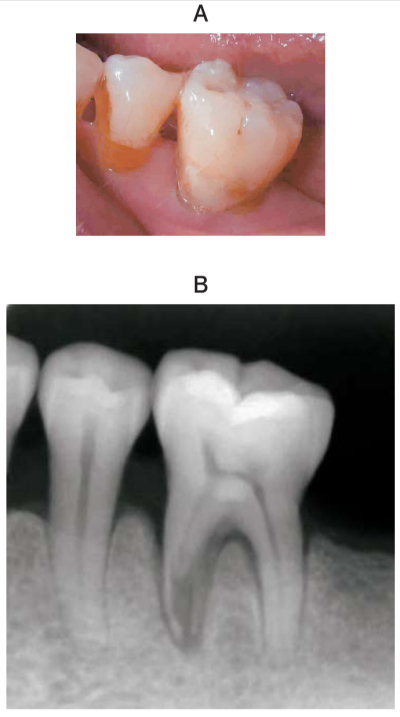

53 歳の男性。下顎左側臼歯部の咬合時の違和感を主訴として来院した。⎾6は打診にわずかに反応するが、根尖部歯肉に圧痛は認めない。歯髄電気診で生活反応を示した。初診時の口腔内写真とエックス線画像を別に示す。歯周組織検査結果の一部を表に示す。

⎾6に対する適切な対応はどれか。1つ選べ。